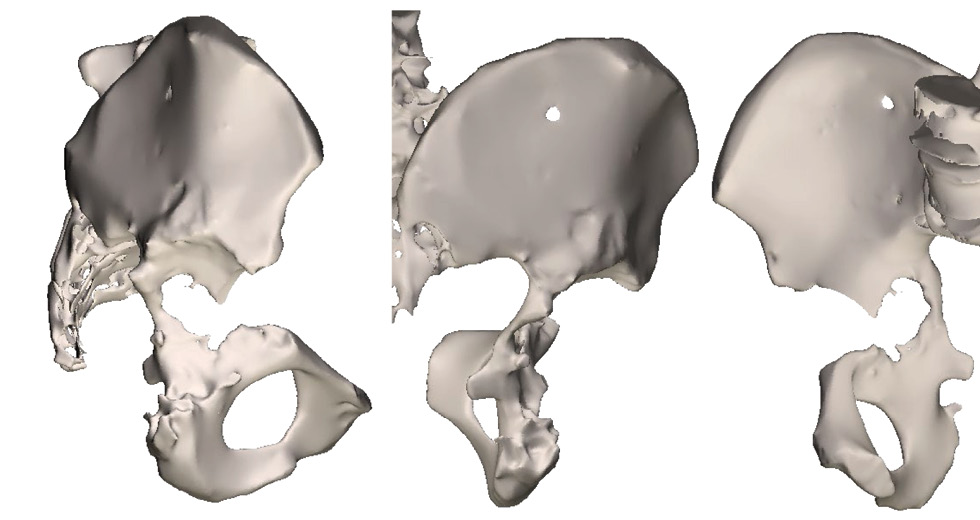

For a more detailed visualization of the defect of the bones forming the acetabulum, multispiral computed tomography (CT) with 3D reconstruction was performed (Fig. 2).

Fig. 2. 3D reconstruction of the right acetabulum by imaging using multislice computed tomography.